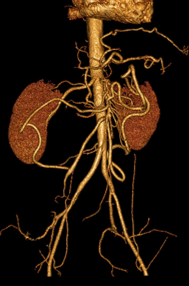

Affections vasculaires abdominales y compris de l'aorte abdominale et de ses branches

DANSE E. & Coll. - UCL - 29/01/2016

Vasculaire Digestif Aorte DES SPECIALITE